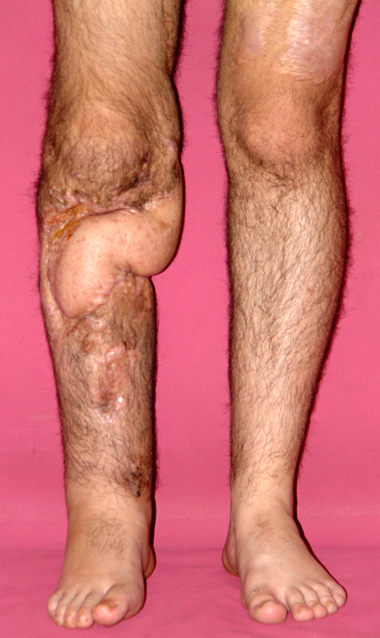

Pseudarthrosis of fracture and pseudarthrosis treatment is currently important problem for orthopedic surgery. Various treatment modalities have been described for pseudarthrosis treatment. All of the treatment methods include high complication rates and additional problems. Leg-length discrepancy, deformity and soft-tissue loss and chronic infection can concomitance with pseudarthrosis. Many internal or external fixation techniques have been described for pseudarthrosis.

Debridement and resection of bone fragment from the pseudarhtosis area vascularized or nonvascularized fibula graft, vascularized muscle flaps, bone grafting followed internal fixation techniques make a option for treatment of pseudarthrosis treatment. But these treatment modalities may not correct deformity and leg-length discrepancy.

Recently, ilizarov techniques which is basis depend on distraction osteogenesis , bone segment transport or acute shortening after the resection at the site of pseudarthrosis combined with lengthening at another level of bone have been used. These treatment techniques may include some advantage for problems of infection, leg-length discrepancy, soft-tissue loss, and joint contracture.